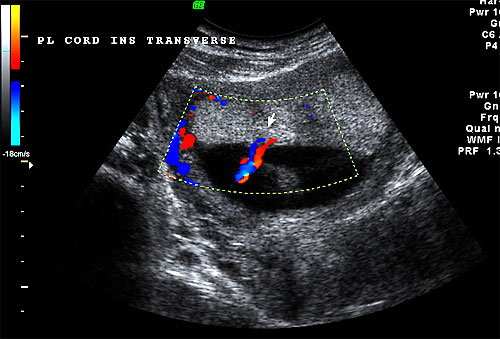

Color flow of central placental cord insertion of 16 week fetus |